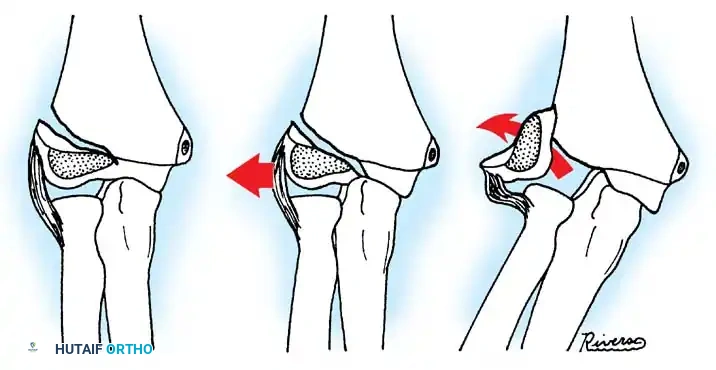

Fractures can present as angulated, translocated (shifted), or totally displaced. In the context of an elbow dislocation, the proximal fragment may become loose within the joint space or trapped, acting as a mechanical block to reduction.

Fig. 33-40 Examples of angulation, translocation, and total displacement of radial neck fractures.

Fig. 33-42 Reduction technique for radial neck fractures.

- Positioning: The patient is placed supine. An assistant firmly stabilizes the distal humerus and the radius distal to the fracture site.

- Maneuver: With the elbow in full extension, the surgeon applies a strong varus stress to the elbow with one hand. This opens the radiocapitellar joint laterally.

- Reduction: Using the thumb of the opposite hand, direct lateral-to-medial pressure is applied over the tilted radial head to lever it back into anatomical alignment.

- Immobilization: The forearm is then placed in 90 degrees of flexion and pronation to lock the reduction.

Fig. 33-45 Mechanism of reduction of radial neck fracture.